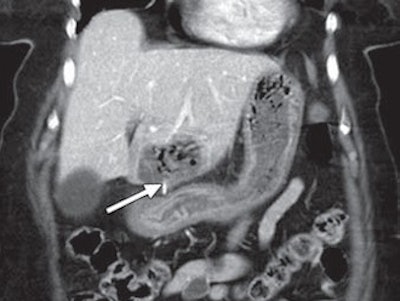

The remaining three patients presented with abdominal pain and underwent CT scans. In two patients, the wire perforated the small intestine. The metal piece perforated through the stomach and into the liver of the third patient and was surrounded by a large hepatic abscess. Laparoscopy was performed on the basis of the CT and clinical findings, and the bristle was removed through surgery.